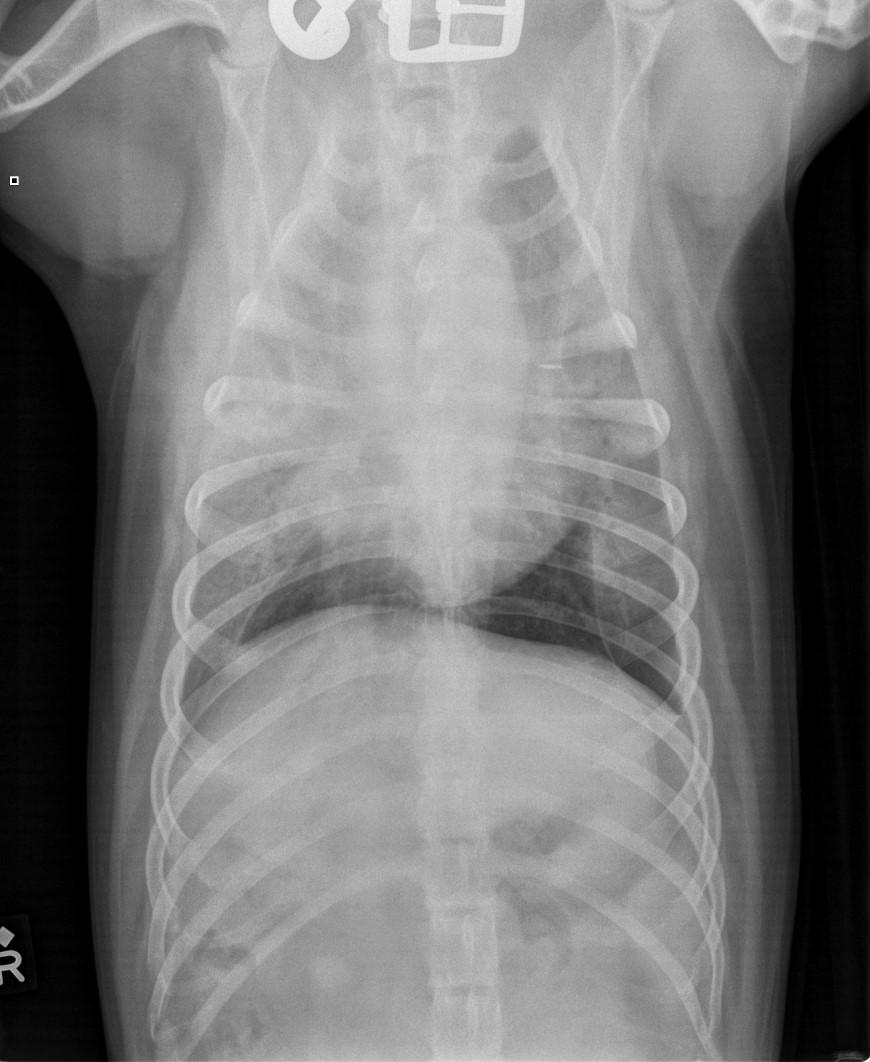

Diagnosis:thoracicradiographs;skinbiopsies –apoptotickeratinocyteswithlymphocyte satelitosis;ruleoutinfections,ectoparasites (Cheyletiella)